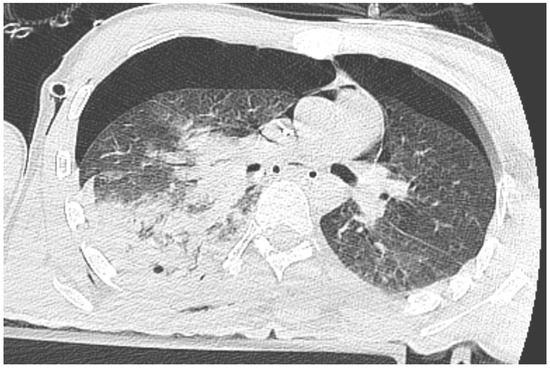

Immediately after decompression, the blood pressure was 134/85 mmHg, the heart rate was 105 bpm, and the saturation was 92%. The critical parameters from the blood gas analyzer just after the decompression of pneumothorax are as follows (11:15 p.m.): pH 7.016, pCO2 45.2 mmHg, pO2 107 mmHg, HCO3 11.6 mmol/L, BE −19.4, anion gap 19.4 mmol/L, and hemoglobin 15.0 g/dL (after transfusion of three units of red blood cells). Laboratory blood tests showed a level of troponin 15,158.657 pg/mL. In the next 30 min, the blood pressure was 85/50 mmHg. Catecholamine infusion was initiated, fluid therapy was continued, and point-of-care ultrasound diagnostics were repeated, Still, we could not obtain the heart from any ultrasound window. A new CT scan was performed with no contrast, and there was bilateral pneumothorax small pneumopericardium in the pericardial cavity (Figure 2 and Figure 3). Drainage of the left pleural cavity was performed. The right drain was oscillating, but it was no longer functional and was trapped in the lung fissure between the expanding lobes of the right lung, which was seen on CT scans. The right pleural drain was replaced, which resulted in an improvement in the patient’s condition. However, he still required the use of catecholamine.

Approximately 50 mL of air was obtained, which resulted in a significant reduction in symptoms despite the persistence of pneumopericardium in the CT scan but without the signs of elevated pressure in the pericardial sac (Figure 6).

Figure 3. CT scan of pneumothorax and pneumocardium after pericardial decompression of the pneumopericardium.